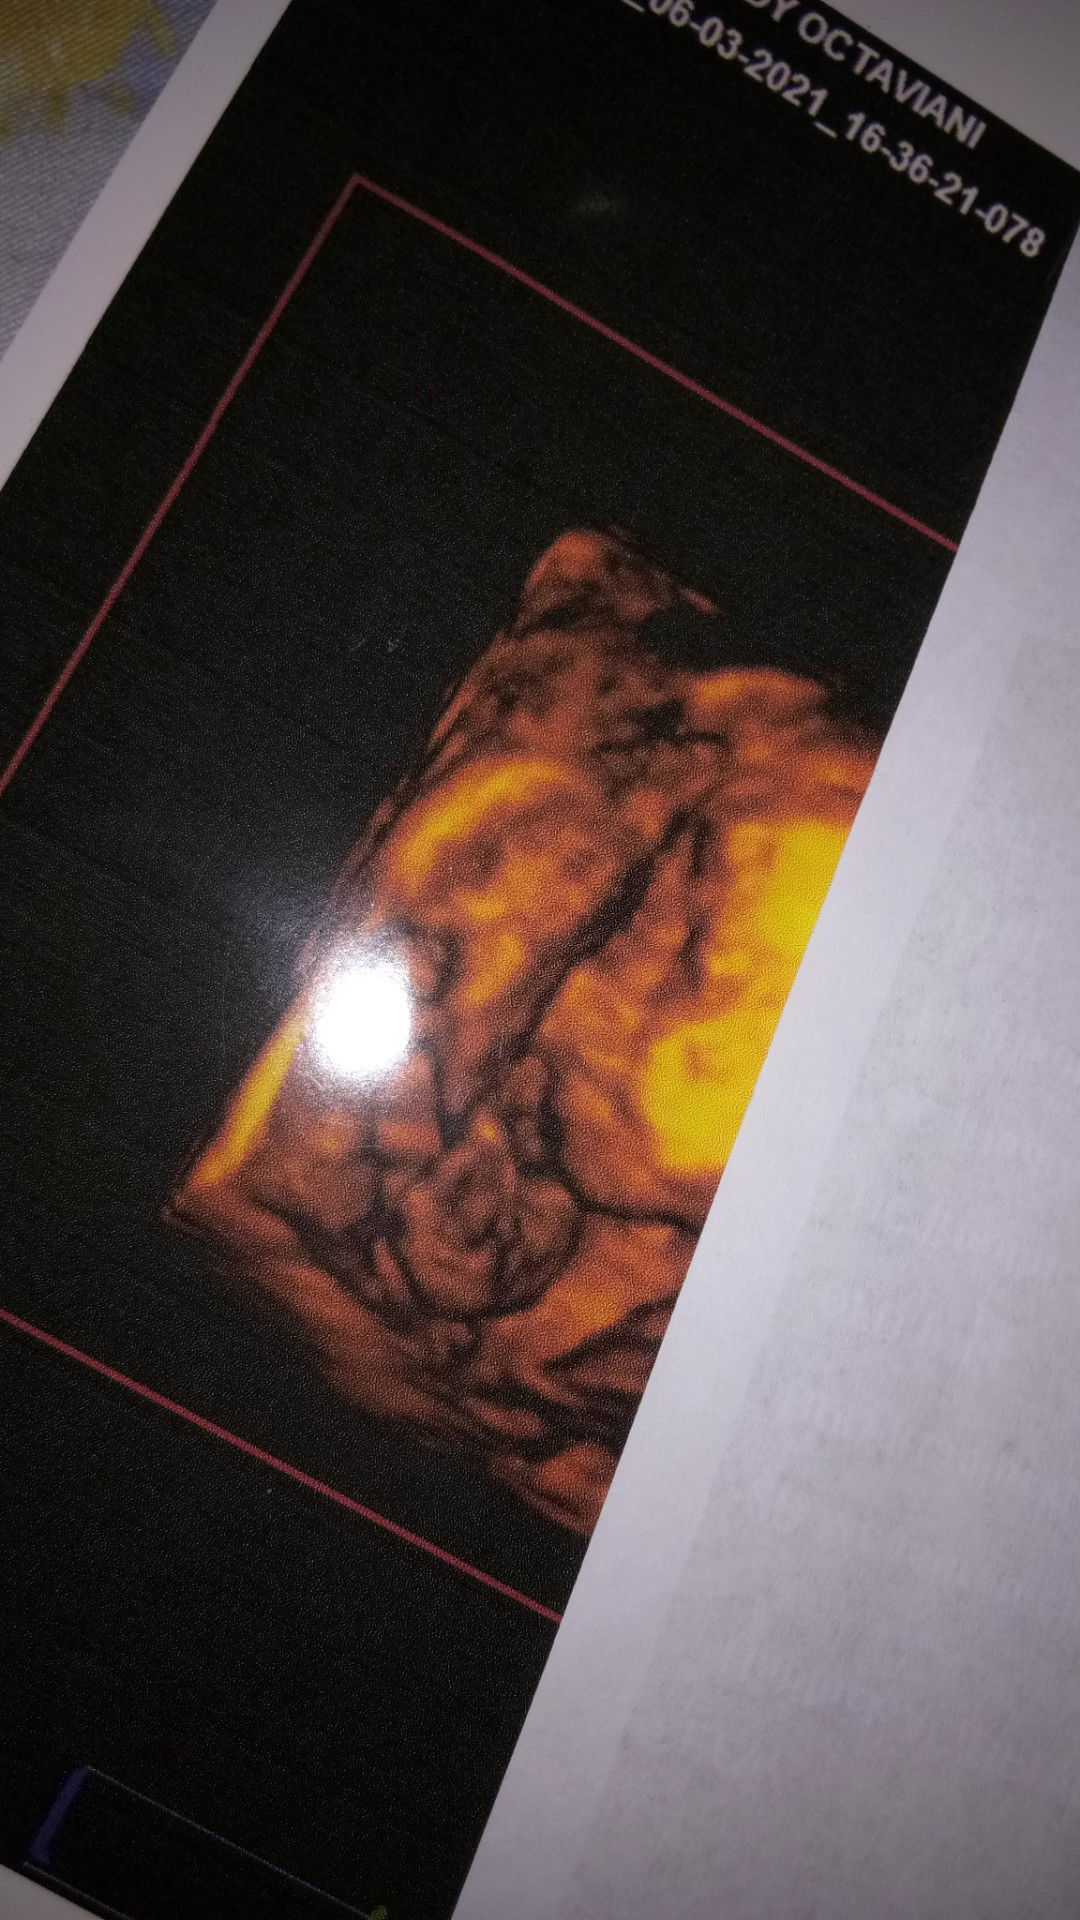

Cindy Octafiani

hpl insyaAllah Juni, 23